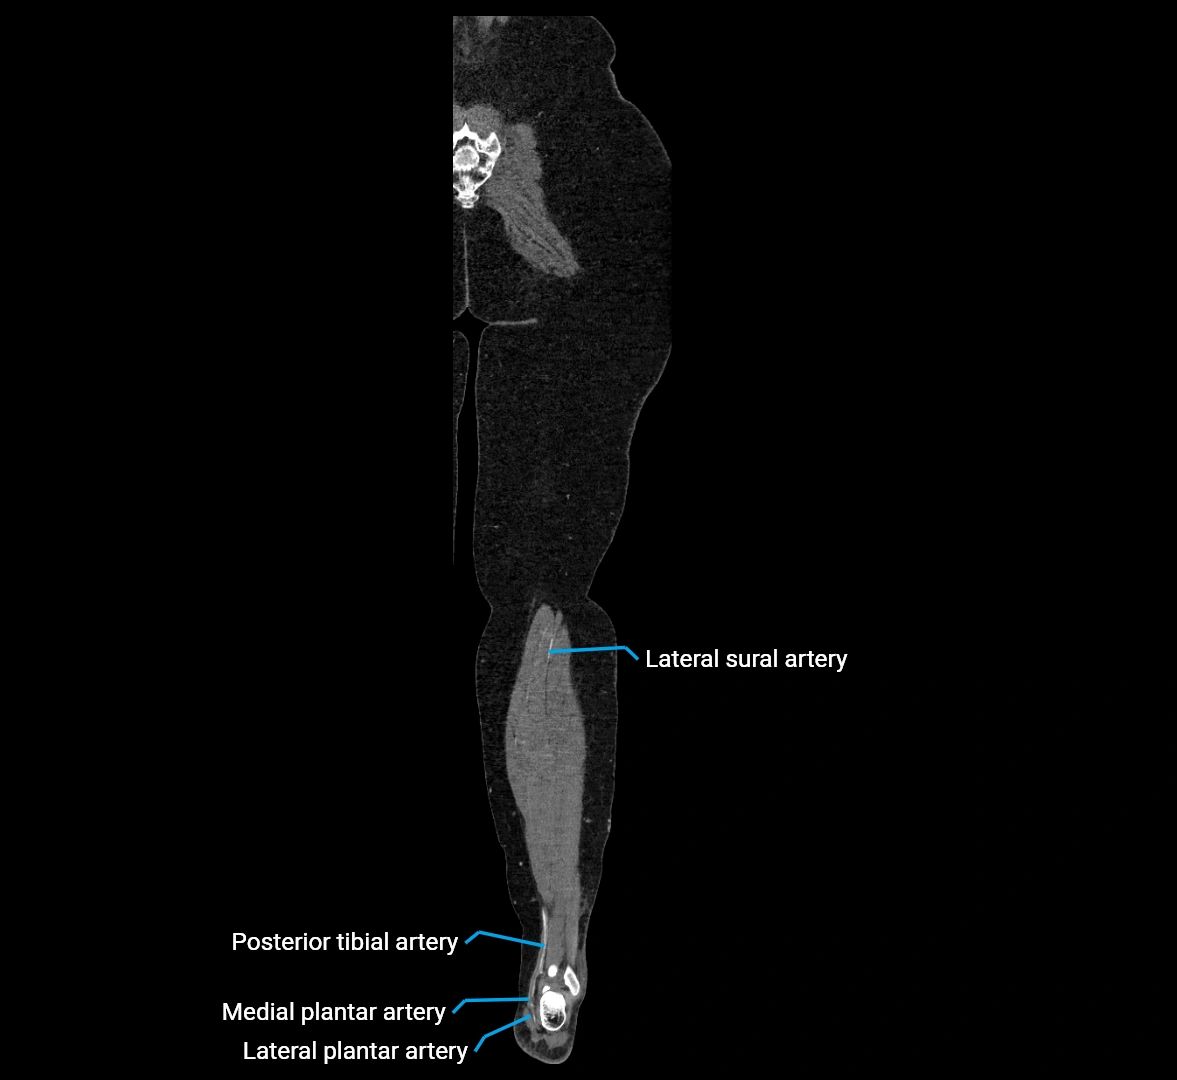

CT images

image

Contrast-enhanced CT (CTA):

• Gold standard for abdominal aortic imaging

• Provides excellent detail of lumen, wall, aneurysm, thrombus, and branch vessels

• Multiplanar and 3D reconstructions help in aneurysm measurement, stent graft planning, and dissection evaluation

• Detects acute rupture, traumatic injury, or occlusion with high sensitivity